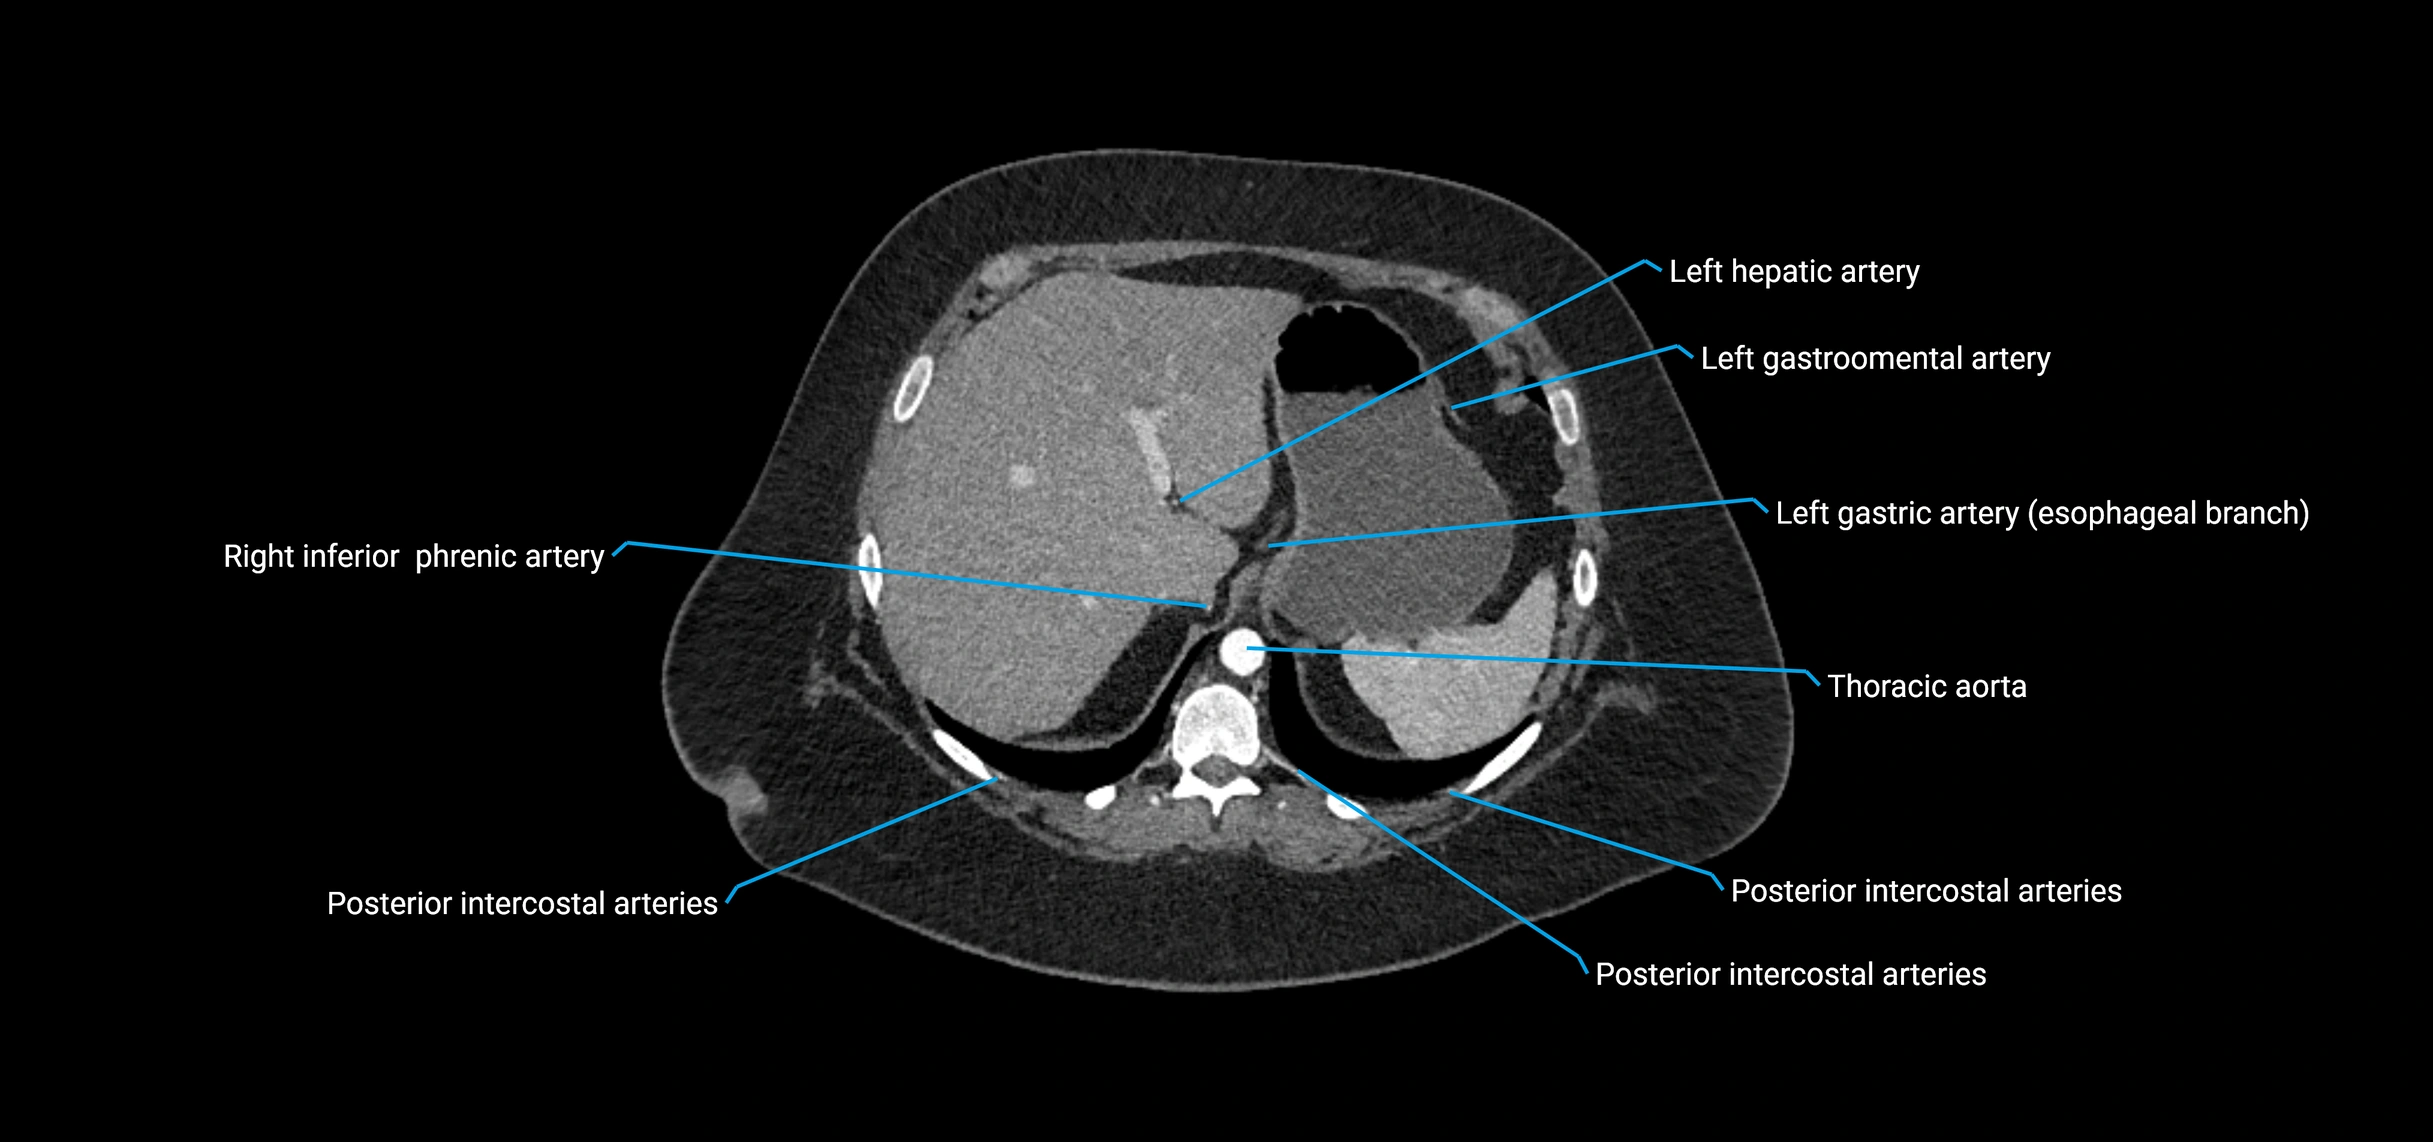

MRI Appearance

T1-weighted images:

• Flowing blood appears as a signal void (black lumen)

• Vessel wall appears as a thin hypointense rim; retroperitoneal fat enhances contrast

T2-weighted images:

• Lumen remains a signal void due to flow

• Adjacent edema, hematoma, or aneurysm wall thrombus may appear hyperintense

T1 Post-Contrast (Gadolinium-enhanced):

• Aortic lumen enhances brightly and homogeneously

• Clearly demonstrates aneurysm, stenosis, dissection, mural thrombus, or aortic wall enhancement in vasculitis

MRA (Magnetic Resonance Angiography):

• Contrast-enhanced MRA provides high-resolution imaging of the aorta and its branches

• Allows 3D reconstruction of visceral, parietal, and terminal branches

• Excellent for evaluating aneurysm size, dissection flap, stenosis, or preoperative planning

• Non-invasive alternative to conventional angiography